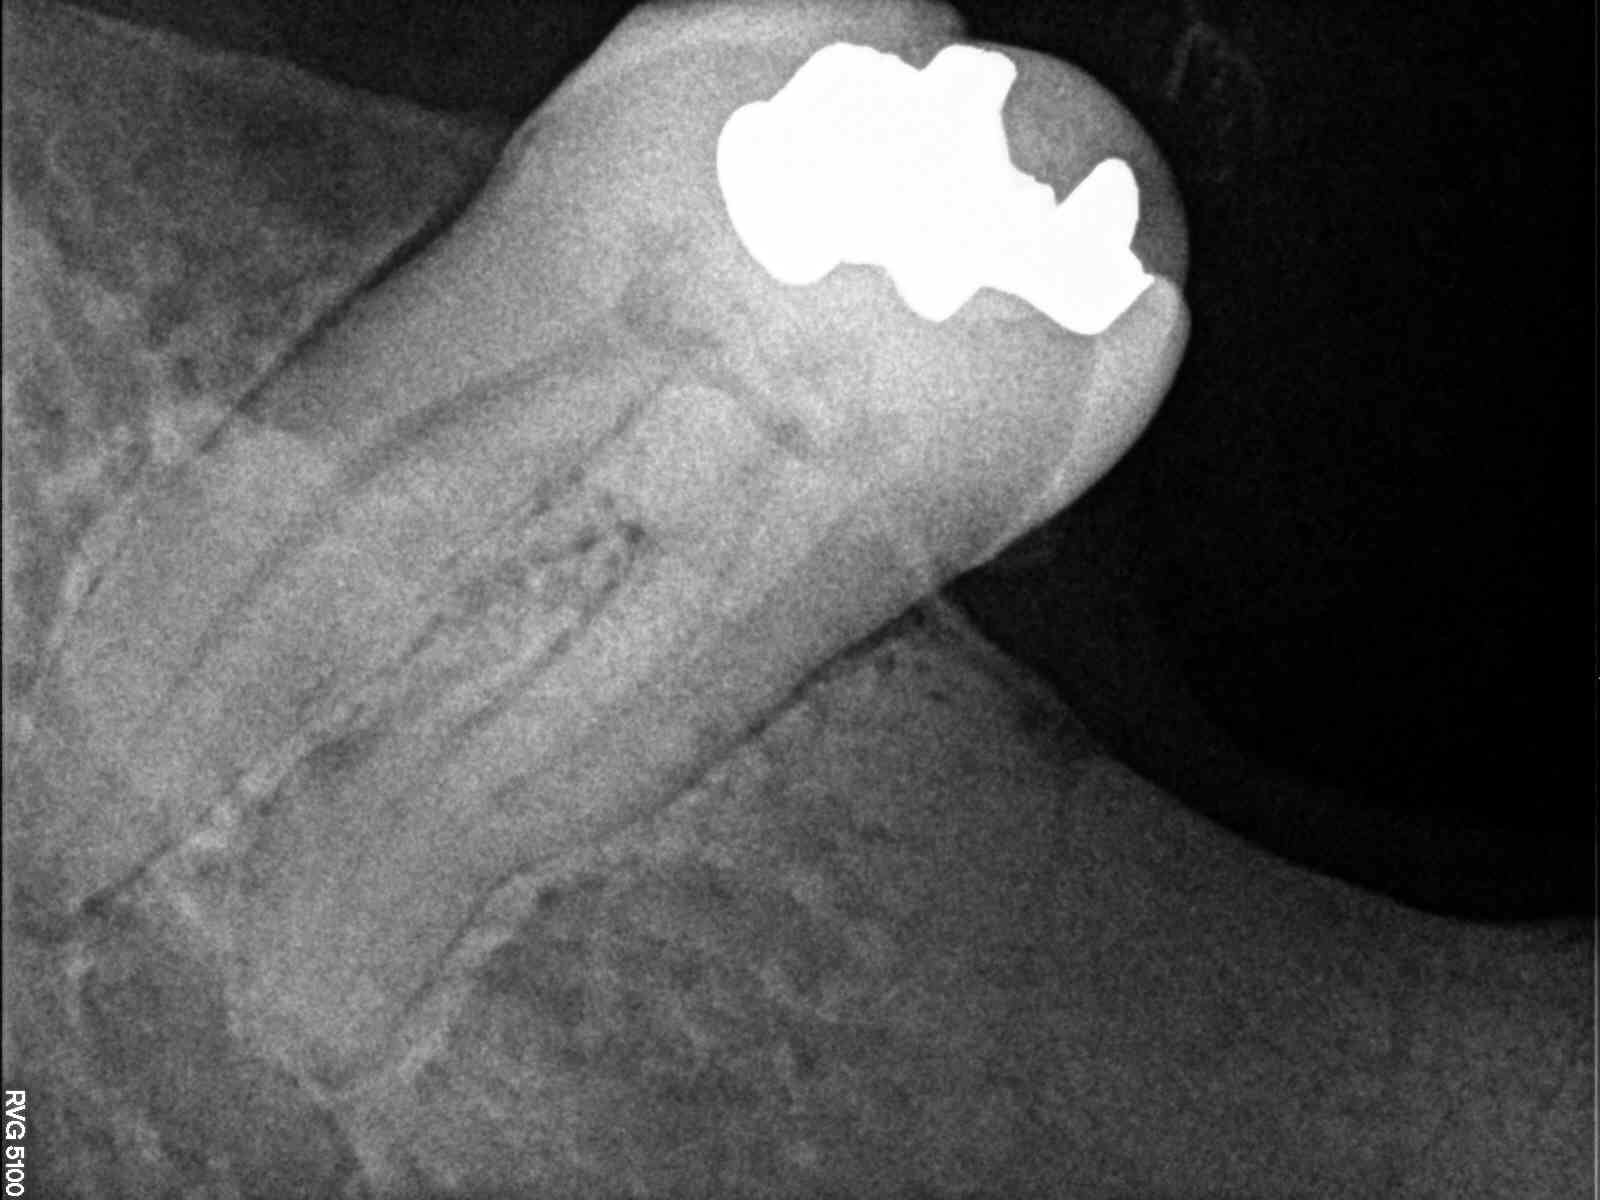

Découverte fortuite à la pano ... gamine de 17ans

Aucun signe clinique SAUF mobilité de 37 qui m'a inquiété .

c est l ameloblastome ???

La maxillo m'a fait un retour en précisant suspicion d'améloblastome.

Update : C'est bien un améloblastome.

Mandibulectomie sectorielle prévue avec reconstitution fibulaire ..

C’est effrayant la vitesse à laquelle ça a progressé 😔